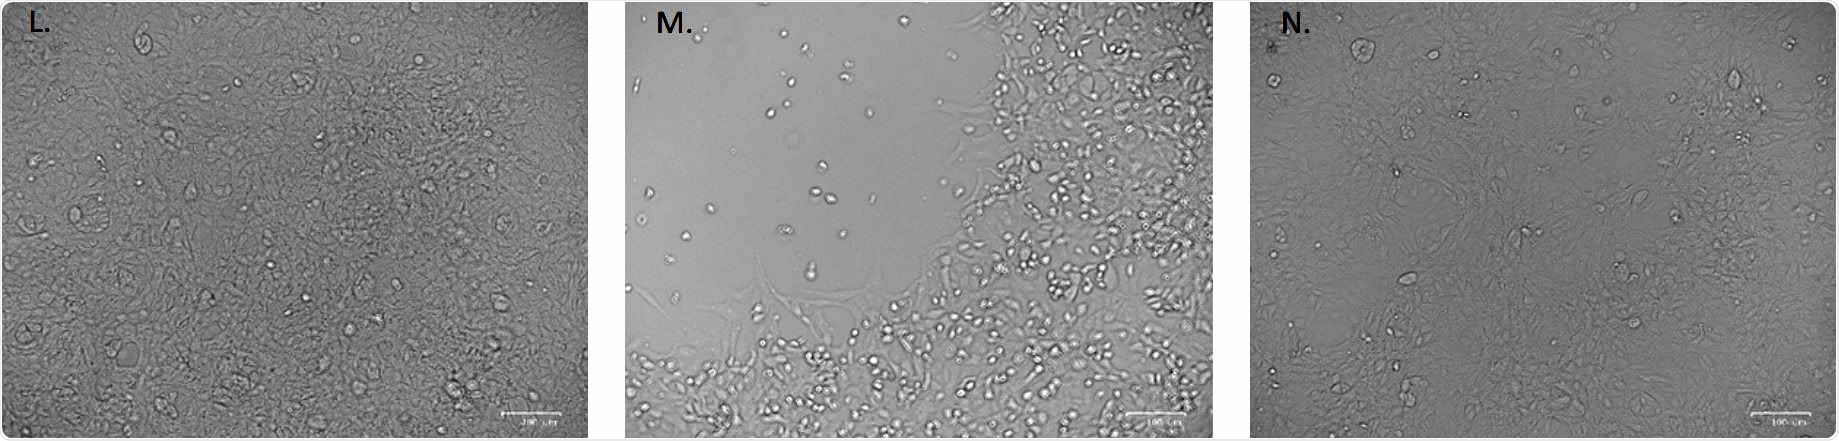

No cytopathic effect was observed in uninfected cultured VeroE6 monolayers maintained in 50mJ/cm2 UVTtreated complete medium for 72 hours. (M) In vitro infection of SARSTCoVT2 (5 MOI) UVTC untreated VeroE6 cells resulted in an evident cytopathic effect. (N) SARST CoVT2 irradiation with 3.7 mJ/cm2 UVTC rescued the cytopathic effect induced by UVTC untreated virus.

At the intermediate contamination level (MOI of 5), viral replication was effectively reduced by this low dose after 24 hours and did not increase over time, indicating a complete inactivation of the virus. Evaluation of cytopathic effects also confirmed virus inactivation.